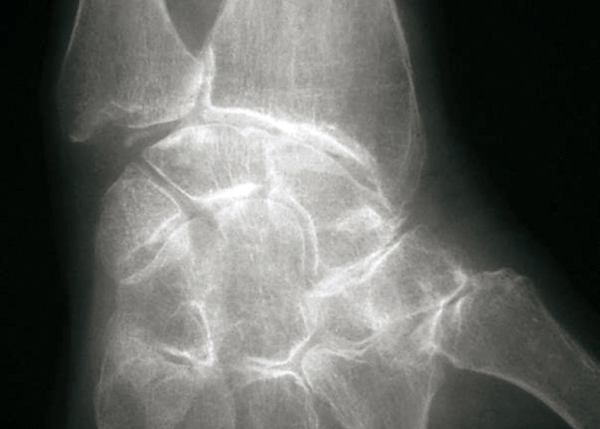

© Gérard Chalès, Pascal Guggenbuhl (La Revue du Praticien) Radiographie du poignet de face. Chondrocalcinose articulaire : calcification du ligament triangulaire du carpe. Extrait de : Chalès G, Guggenbuhl P. Arthropathie microcristalline. Rev Prat 2013;63(5):709-20.